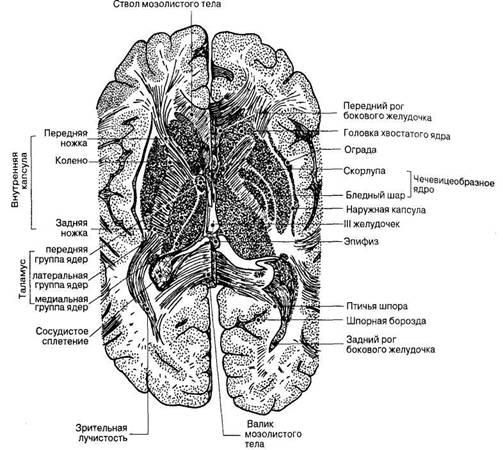

Необычные объекты: Переднее продырявленное вещество

Раздел: Альбом открытий